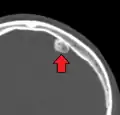

يمثل الورم العظمي أكثر أورام الأنف والجيوب المجاورة للأنف من حيث كونها حميدة. سبب الإصابة بالورم العظمي غير مؤكد، لكن النظريات المقبولة بشكلٍ عام تقترح أسباباً جنينية أو رضحية، أو معدية. كما قد يترافق الورم العظمي مع متلازمة غاردنر. قد تتسبب الأورام العظمية القحفية الأكبر حجماً بحدوث ألم في الوجه وصداع وعدوى بسبب انسداد القنوات الجبهية الأنفية. غالباً ما يظهر الورم العظمي القحفي الوجهي من خلال علامات وأعراض في العينين كجحوظ العين.[2]